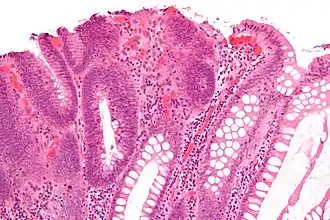

| Hyperplastic polyp | 0% | No dysplasia.[10]

Hyperplastic polyp

Most hyperplastic polyps are found in the distal colon and rectum.[18] They have no malignant potential,[18] which means that they are no more likely than normal tissue to eventually become a cancer.

Microvesicular hyperplastic polyp. H&E stain.

Microvesicular hyperplastic polyp. H&E stain. -

Microvesicular hyperplastic polyp. H&E stain.

Microvesicular hyperplastic polyp. H&E stain. -